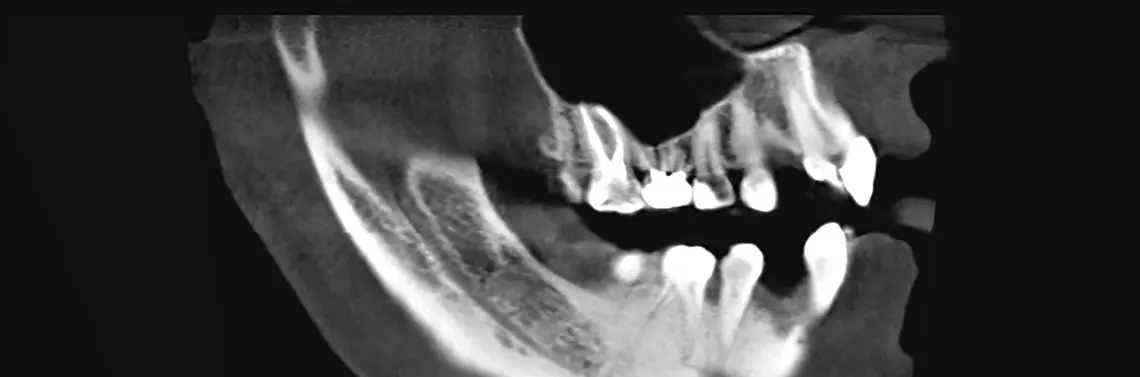

W przedstawionym przypadku, w którym nastąpiła utrata zęba w położeniu 45. (zdj. 1–40), zachodził proces gojenia ze zbyt małą ilością materiału dla tworzenia tkanki na nowo przy braku ściany przedsionkowej. Tym samym utrata zewnętrznej warstwy korowej prowadziłaby do zaniku sygnałów decydujących o tworzeniu się kości i doszłoby do utraty tkanki twardej z uwagi na brak stabilizacji trójwymiarowej.

Pacjentka zgłosiła się w celu przeprowadzenia zabiegu augmentacji zębodołu po 14 dniach od usunięcia zęba, ponieważ ze względów medycznych nie była możliwa natychmiastowa augmentacja z typem III według klasyfikacji poekstrakcyjnych ubytków wyrostka zębodołowego. Jest to najtrudniejszy do leczenia rodzaj defektów wyrostka, który wymaga zabiegów augmentacji i często wieloetapowej metody, co jest czasochłonne.

Po 6 miesiącach wykonano tomografię komputerową stożkową zębów 3D (CBCT) w celu określenia jakości kości w miejscu przeprowadzonej augmentacji i zaplanowania dalszych zabiegów. Metody obrazowania trójwymiarowego pozwalają na przeprowadzenie diagnostyki przestrzennej bez zniekształceń. Technika ta pozwala na przeprowadzenie diagnostyki i dokładnego planowania z uwzględnieniem wszystkich struktur anatomicznych. W przypadku objętościowej tomografii komputerowej pacjentka znajdowała się z pozycji siedzącej. Źródło i detektor były prowadzone w jednej płaszczyźnie wokół pacjentki. Promień miał kształt stożka i obrazuje pole o wysokości 7 cm i szerokości 14 cm. Za pomocą diagnostyki trójwymiarowej można poza tym odnaleźć podcienie, z których obecnością nie liczymy się w przypadku wystarczającej ilości kości w obrębie wyrostka zębodołowego.

Dla większych obszarów, np. ząb zatrzymany, nie mają większego znaczenia. Wyjaśnia to, jak ważne było przygotowanie pacjentki do badania tomografii komputerowej. Dokładne wyjaśnienie przebiegu badania oraz jego zrozumienie pozwala uniknąć wielu błędów. Dokładne pozycjonowane i współpraca pacjentki dały bardzo dobre efekty. Zdjęcia przedstawione w artykule wykonano w średniej rozdzielczości o wielkości woksela 0,278 mm3 oraz 36 warstw DICOM/cm.